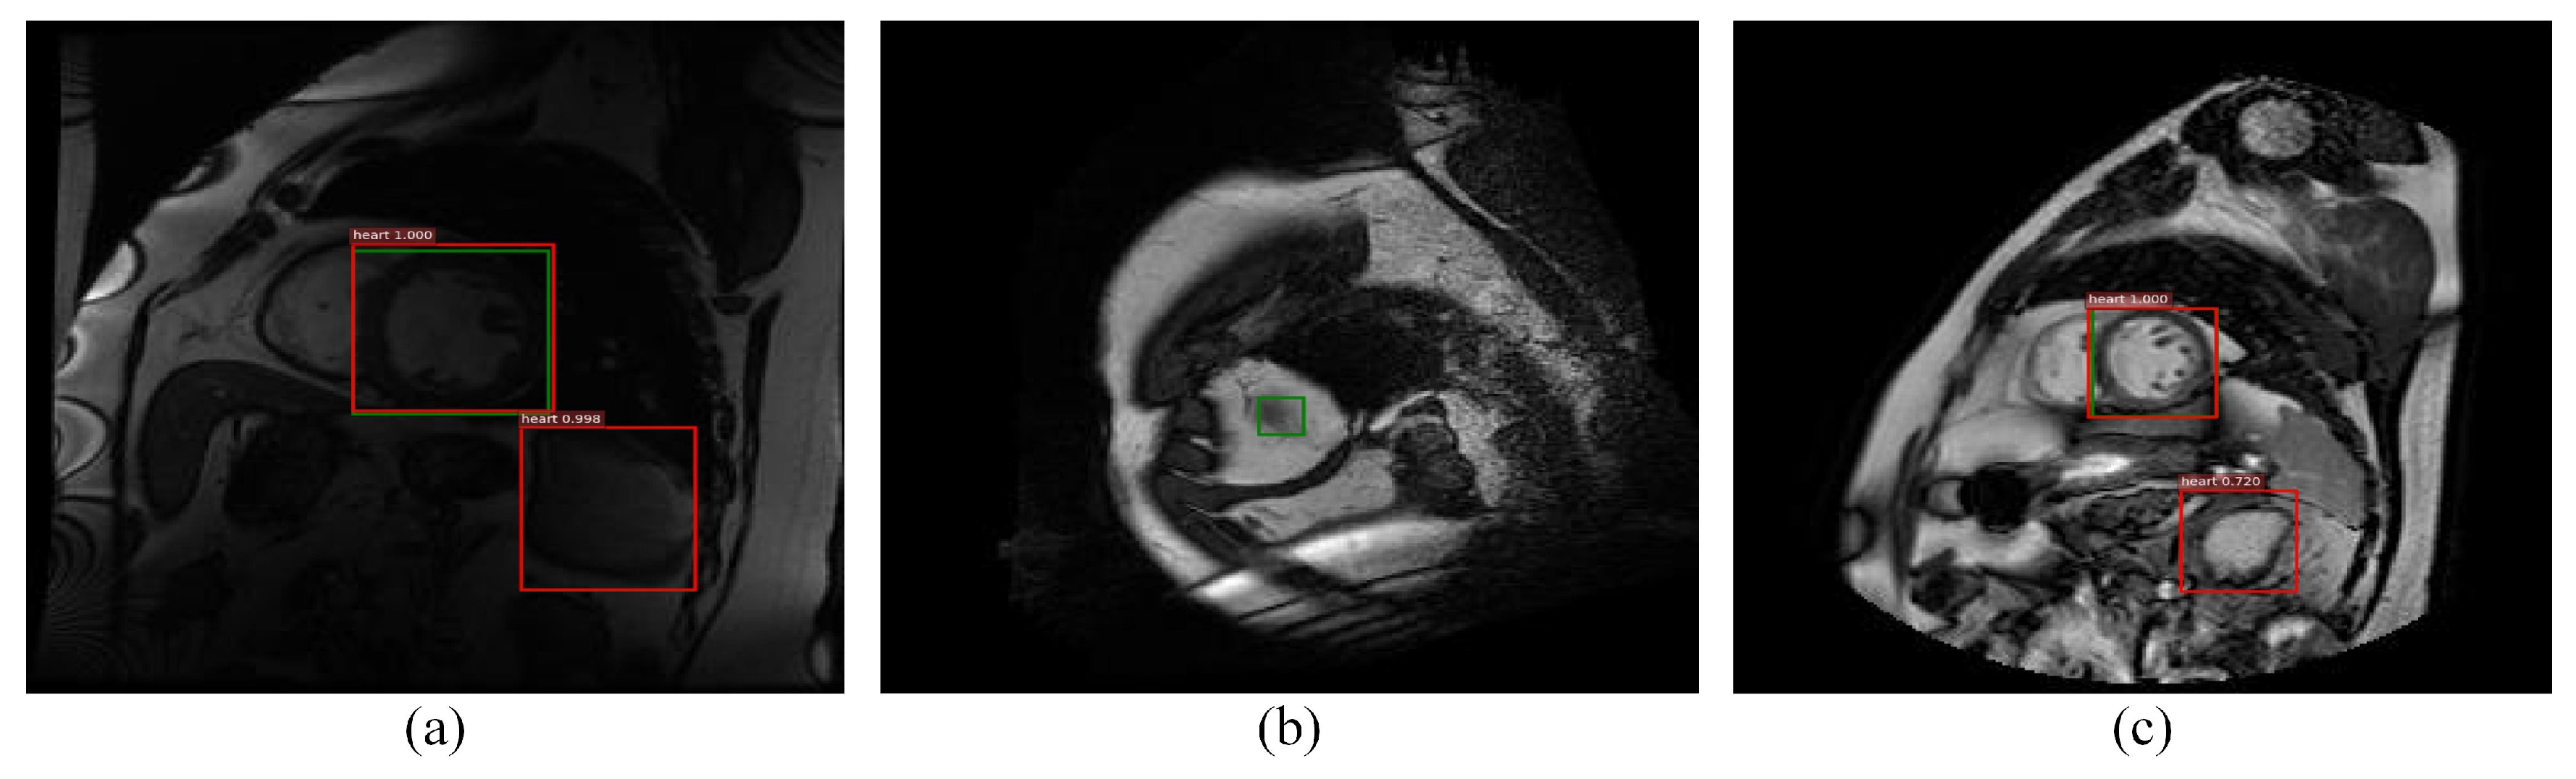

The detection performance of the proposed method is significantly improved in comparison to Faster RCNN, which can effectively prevent false detection and missed detection. The comparison with a series of detection methods validates the effectiveness of the improved method in this paper. However, due to the complex tissue and organ distribution in MRI, the shape characteristics of some left ventricle areas are not obvious, and some areas are highly similar to the left ventricle; it is inevitable that a small amount of missed or false detection will occur. Figure 13 reports some examples of false or missed detection by the proposed method.

Figure 13.

Examples of false or missed detection in the proposed method, where (a,c) are examples of false detection, and (b) is an example of missed detection. The green boxes and red ones denote the label and detection results, respectively.

As can be seen from the figures above, the occurrence of pseudo-detection is mainly in areas where the appearance is similar to that of the left ventricle. Missing detection mainly occurs in the area where the the left ventricle shape features are not obvious and the size is too small. In further research, the adaptive and discriminant dictionary learning will be investigated for this challenging case.